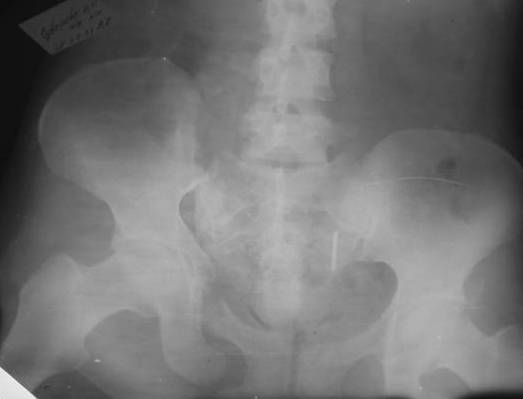

Пациентка С.26 лет. Травма за 6 месяцев до поступления

Укорочение правой нижней конечности до 10см

Маленькая иллюстрация (около 5 лет после травмы). Результат плохой - укорочение, хромота, периодически боли в спине, но больной отказывается от операции, видимо, не так все трагично.